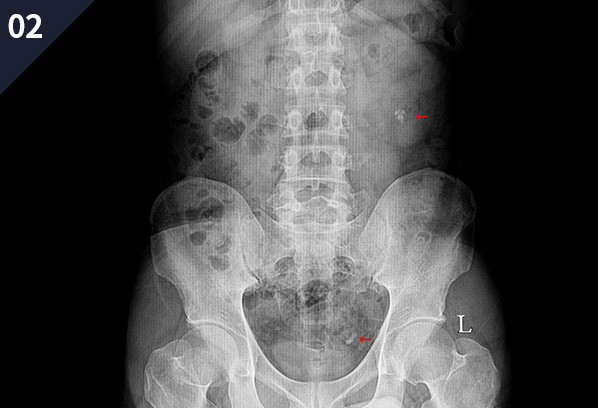

¿ä·Î°á¼®ÀÇ ¿©ºÎ ¹× À§Ä¡¸¦ ÆÄ¾ÇÇÏ´Â